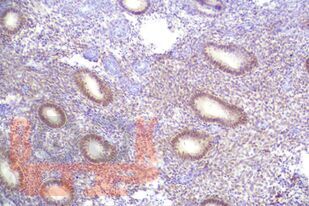

Учебное пособие содержит материалы, касающиеся терминологии, распространенности, современных классификационных принципов, морфологии и терапии эндометриальных полипов. Пособие составлено в соответствии с рабочими программами дисциплин «Патологическая анатомия», «Акушерство и гинекология» и разработано с учетом положения «Требования к структуре, содержанию и порядку оформления учебных изданий» СМК П 13-2019, утвержденного приказом ректора ФГБОУ ВО ЮУГМУ Минздрава России от 30.08.2019 № 215, введено в действие с 02.09.2019.